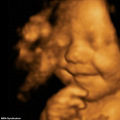

英国一位名为里昂·哈格里夫斯的小宝宝一定非常喜欢这个世界。因为他从出生前到出生后,一直“笑嘻嘻乐呵呵”的,显得相当幸福。 据悉,这名宝宝的父母相信,他们的孩子一定是英国最幸福的,因为他一直在不停的微笑。在孩子母亲怀孕31周时,她曾前往医院做了超声波成像,然而令她和...